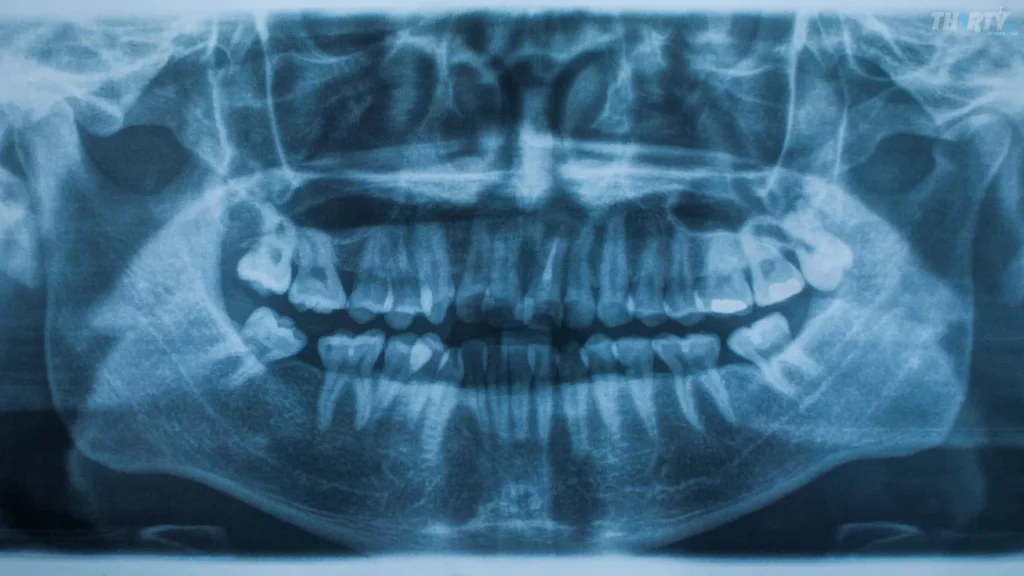

الأشعة البانورامية Panoramic X-ray نوع من الأشعة السينية وهي تقنية تصوير شعاعي تُستخدم في طب الأسنان للحصول على صورة شاملة ثنائية الأبعاد (Two-Dimensional Image) لجميع الأسنان وللـ الفكين العلوي والسفلي والمفاصل الصدغية الفكية (Temporomandibular Joints – TMJ) في صورة واحدة وتعتمد هذه التقنية على استخدام جهاز خاص يُسمى جهاز الأشعة البانورامية (Panoramic X-ray Machine) حيث يدور مصدر الأشعة (X-ray Source) وكاشف الصورة حول رأس المريض في حركة دائرية لالتقاط صورة متكاملة للمنطقة الفموية بأكملها وتُعرف هذه الأشعة أيضًا باسم الأشعة السينية الكاملة للفم (Full Mouth X-ray) أو بانوراماكس (Panorex).

وتتميز الأشعة البانورامية بقدرتها على تقديم معلومات تشخيصية مهمة مثل تحديد موقع ووضع الأسنان الدائمة واللبنية واكتشاف التسوس (Dental Caries) وتقييم حالة اللثة والعظام الداعمة (Periodontal and Bone Conditions) وتحديد وجود أي مشكلات هيكلية مثل الكسور (Fractures) أو الأكياس السنية (Cysts) أو الأورام (Tumors) في منطقة الفكين.

وتُعتبر هذه الأشعة أداة تشخيصية مهمة للأطباء الأسنان لتحديد الأمراض والمشاكل السنية المخفية التي قد تكون غير مرئية في الفحوصات العادية ويتم تنفيذ الأشعة السينية البانورامية بطريقة آمنة وسريعة وتتطلب القليل من التحضير الخاص حيث يتم إعطاء العرض الطبيعي للجسم باستخدام مرطبة من الرصاص للحماية من الإشعاع الزائد وتُعتبر الأشعة السينية البانورامية أداة فعالة لتقييم الصحة الفموية الشاملة وتحديد العلاجات المناسبة للمرضى وعلى الرغم من أنها توفر صورة شاملة إلا أن الأشعة البانورامية لا تُظهر التفاصيل الدقيقة التي يمكن الحصول عليها باستخدام تقنيات أخرى مثل الأشعة السنية أو التصوير المقطعي المحوسب (CT Scan).